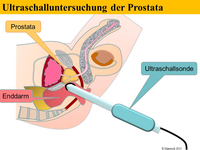

Im Allgemeinen spürt man den beginnenden Prostatakrebs nicht. Krankheitsspezifische Symptome werden erst in sehr späten Phasen der Erkrankung entwickelt. Um diese Symptome und die ernsthaften Folgen einer solchen Erkrankung zu verhindern, versucht man die Erkrankung frühzeitig zu diagnostizieren. Die wichtigsten diagnostischen Instrumente zum Nachweis eines Prostatakrebses sind die digital-rektale Untersuchung (DRU: Tastuntersuchung mit dem Zeigefingers des Arztes über den Enddarm), der PSA-Serumwert (ein Wert der durch eine einfache Blutabnahme ermittelt wird) und die transrektale Ultraschall-gesteuerte oder –gezielte Biopsie der Prostata.

Die Methoden Ultraschall-Elastographie, der farbkodierte Doppler-Ultraschall sowie der kontrastmittelverstärkter Ultraschall und insbesondere die Echtzeit-MRT-Ultraschall-Fusion können helfen, auffällige Gebiete in der Prostata aufzuzeigen. So kann zum Beispiel ein in einer MRT (Magnetresonanztomographie) gefundener suspekter (also auffälliger) Bereich ganz gezielt biopsiert werden und auch zusätzlich noch elastographisch untersucht werden. Dies ist während einer herkömmlichen MRT-Untersuchung nicht möglich.

Eine multimodale Prostataabklärung erlaubt uns, die Prostata mittels modernster Verfahren zu untersuchen. Hierbei kommen verschiedene Untersuchungsmethoden zur Anwendung. Insbesondere die Echtzeitelastographie oder die kontrasmittelunterstützte Untersuchung der Prostata können hierbei wichtige Erkenntnisse über die Beschaffenheit der Prostata beisteuern. Auffällige Areale können in Echtzeit schmerzfrei mit lokaler Betäubung abgeklärt werden. Als Besonderheit können diese modernen Methoden auch mit einer bereits durchgeführten MRT-Untersuchung der Prostata fusioniert werden. Das bedeutet, in einer MRT gefundene auffälligen Areale der Prostata können zusätzlich mit modernsten Ultraschalluntersuchungen kombiniert untersucht werden und dann auch gezielt mittels gezielter Prostatabiopsie abgeklärt werden. Diese Untersuchung ist dann multimodal (zB Elastographie + konventionellem Ultraschall + MRT-Fusion).

Zunächst einmal werden die bereits durchgeführten und von Ihnen mitgebrachten MRT-Bilder (1,5T-3T, mit/ohne rektale Spule, DICOM-Format) in unser Gerät eingelesen. Anschließend werden die suspekten Areale und die Organgrenzen der Prostata in der MRT-Bildgebung markiert. Nun beginnt der praktische Teil: In angenehmer Seitenlage wird über einen modernen transrektalen Ultraschall die Prostata aufgesucht und anhand der Anatomie der Prostata mit dem MRT Bild fusioniert. Der Untersucher sieht nun auf der linken Seite des Flachbildschirmes des Ultraschallgerätes das Original-MRT-Bild mitsamt des Markierungen und auf der korrespondierenden rechten Seite die Live Ultraschallbilder in denen die Markierungen der MRT-Untersuchung zu sehen sind. Die auffälligen Areale können nun einer Elastographie oder einer Kontrastmittel-Untersuchung unterzogen werden um den Grad der Auffälligkeit zu bestimmen. Auf Wunsch können auch jetzt gleich die Biopsien durchgeführt werden.